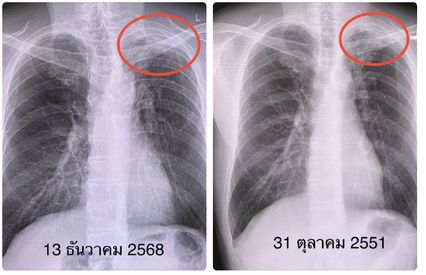

แพทย์ตรวจร่างกาย ไม่มีไข้ ฟังปอดปกติ เอกซเรย์ปอด มีรอยแผลเป็นที่ยอดปอดข้างซ้าย ไม่เปลี่ยนแปลงจากเอกซเรย์ปอดเมื่อ 18 ปีก่อน ส่งเสมหะย้อมเชื้อไม่พบเชื้อ AFB  ส่งเพาะเชื้อ ขึ้นเชื้อวัณโรค ไวต่อยาทุกตัว

เคสนี้แพทย์วินิจฉัย ว่าวัณโรคปอดกลับมาเป็นใหม่ หลังจากเคยติดเชื้อ และได้รับยารักษาเมื่อ 63 ปีที่แล้ว แต่ยาสมัยนั้นอาจไม่ดีพอ ไม่สามารถกำจัดเชื้อให้หมดไปได้ เมื่ออายุมากขึ้น เชื้อวัณโรคที่แฝงในร่างกายสามารถเจริญเติบโตใหม่ได้อีก